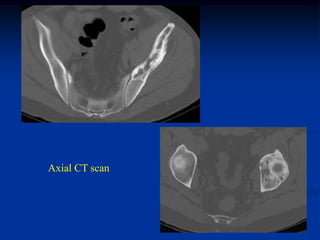

Case #429.2

EG pelvis

39 year male with dull aching pain left hip for 9 mos.

Axial CT scan

Cor and Sag CT

Axial

T-1                   T-2

Cor T-1

Sag T-2